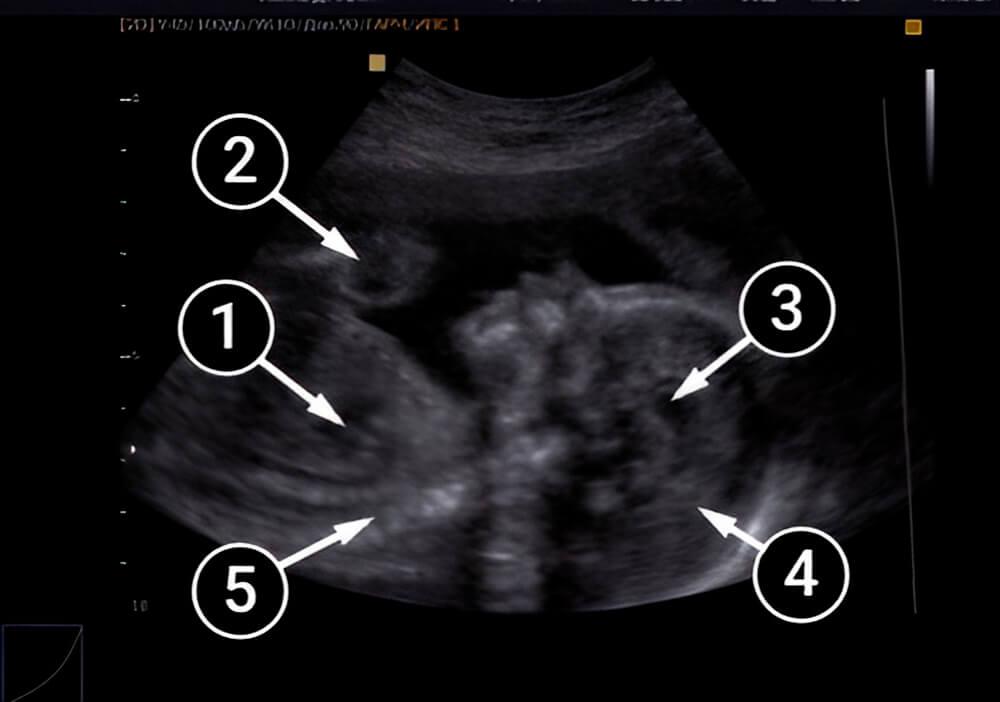

¿Qué se puede ver en la ecografía/ultrasonido?

En la imagen, el bebé se recuesta de costado y en el lado derecho de la foto se ve claramente su cabeza. El área oscura en su centro es el cuerpo calloso, un plexo de fibras nerviosas que divide la corteza cerebral en los hemisferios izquierdo y derecho. Asimismo, se ve una mano que se acerca a la boca; lo más probable es que el bebé quiera chuparse el dedo. Su mano está apretada en un puño.

La mancha oscura en el área del pecho es el corazón, y el arco de luz, ubicado justo debajo, es la curva de la columna.